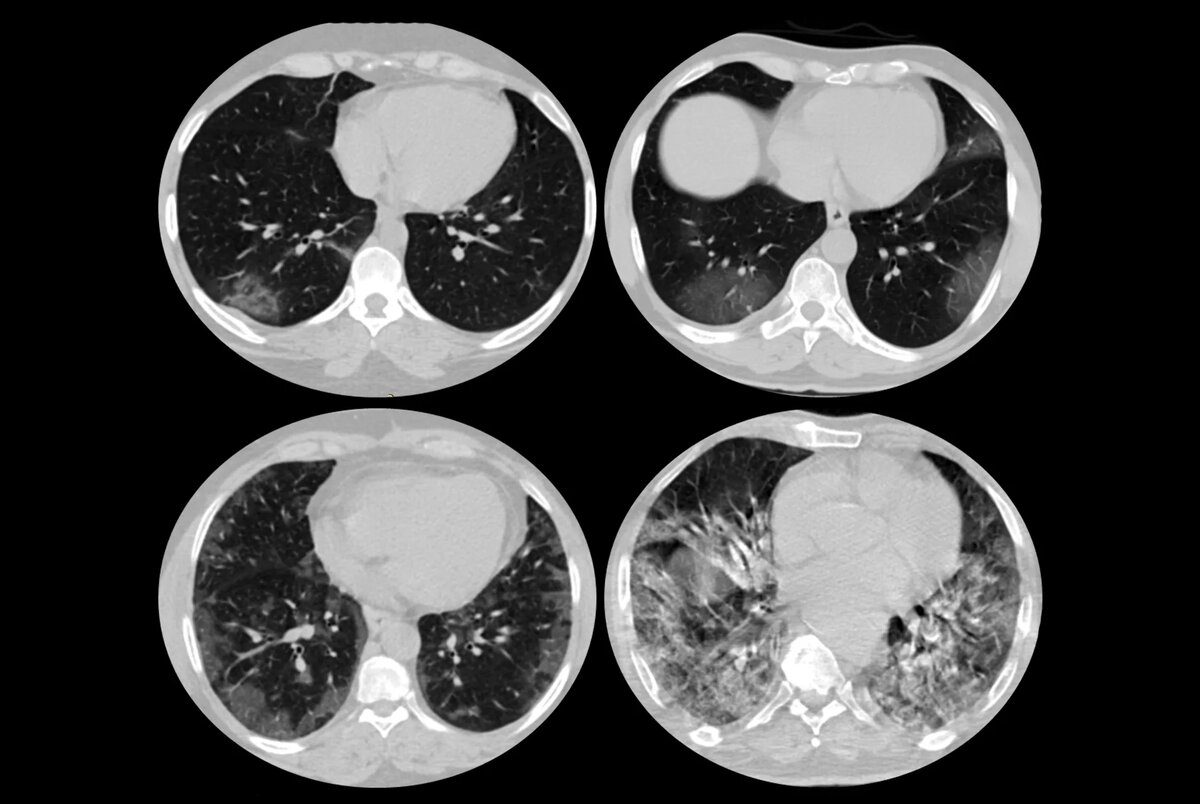

Медицина# COVID-19# SARS-CoV-2# брадикинин# коронавирусКТ легких пациента с Covid-19 / © IAEA

«На первой стадии, во время которой легкие наполняются жидкостью, сканы КТ выглядят очень плохо и пациенты испытывают одышку, — говорит один из авторов работы Франк ван де Веердонк. — Такая картина не может быть объяснена исключительно инфекцией в легких». Симптомы начальной стадии натолкнули исследователей на мысль о том, что скопление жидкости вызвано протеканием капилляров.